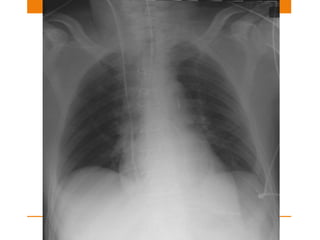

Normally placed CVC

CENTRAL VENOUS CATHETER Function •To monitor right atrial pressure • Fluid infusion/ nutrition • Drug administration Position • SVC or Brachiocephalic vein